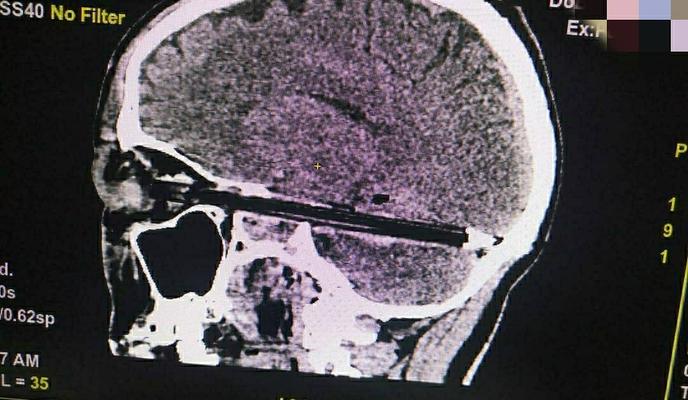

В Ростове-на-Дону врачи спасли пациента с шариковой ручкой, полностью вошедшей в головной мозг. Внутрь черепа канцелярское устройство попало через глаз.

На днях в Городскую больницу скорой медицинской помощи экстренно поступил пациент с шариковой ручкой в глазу. Как показал рентген, канцтовар проник 37-летнему мужчине в головной мозг на весь диаметр от передней до задней черепных ямок.

Как сообщили в пресс-службе ГБСМП Ростова-на-Дону, шариковая ручка вошла в глаз и череп пострадавшего в миллиметре от одного из самых важных сосудов и ствола головного мозга. Предмет был успешно вытащен с предельной осторожностью, при его извлечении дополнительных повреждений не появилось.

В настоящее время мужчина находится в реанимации. После операции врачи также провели обследование на КТ для исключения дополнительных рисков.